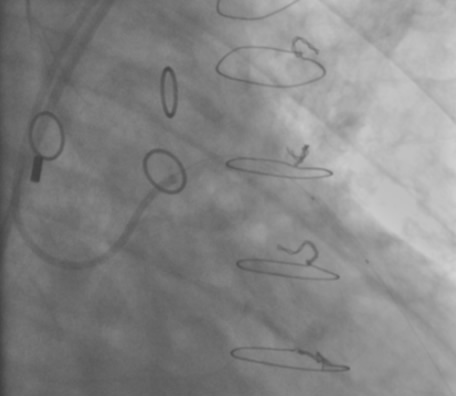

In the past, surgeons used rings to mark the ostia of the vein grafts substantially aiding the angiographer to localize the vein graft ostia during angiography. However, nowadays, it is not a usual practice. The lack of marker can increase the contrast use and radiation particularly in patients without the knowledge of the types and number of vein grafts. As mentioned earlier, right coronary grafts have usually a right sided take off from the aorta. Therefore, using standard view, left anterior oblique (LAO), which is used for right coronary artery catheterization is the view of choice. Left coronary bypass grafts have usually anterior take off. Therefore, a right anterior oblique (RAO) makes it easier to engage the left-sided vein graft ostia preventing foreshortening of the catheter tip. Using RAO, the catheter tip should be oriented to the right side of the screen. The vein grafts to the left system is based on the anatomical proximity of the native coronary to the aorta. Therefore, LAD graft ostia are usually closest grafts to the aortic valve followed by diagonal and circumflex grafts. Circumflex graft ostia usually have the highest take off from the aorta. There are occasional cases with different take off making vein graft angiography difficult. In such a situation, the angiography catheter has to be probed across the aorta in different level in order to engage the ostial vein graft. A non-selective strong contrast injection or aortogram may be necessary to delineate the unusual take off of missing vein grafts or documenting total occlusion of missing vein grafts. Total occluded vein grafts usually have a residual knob in the aorta that can be seen during angiography.

PCI of the vein and arterial grafts have unique challenges. For any PCI, guide support is very important for successful balloon and stent delivery. In a tortuous vein graft with a steep angle, advancement of a stent can be very difficult and challenging. Therefore, it is important to choose the best available catheter before starting PCI. Similar to the right coronary angiography, a JR4 guide catheter is most commonly used in this setting. However, Amplatz guide catheters for left vein grafts and multipurpose catheters for right vein grafts are better choices in certain anatomy. In Figure 8 and Figure 10 two examples of poor guide support in two vein graft interventions can be seen. Initially, a JR4 guide was used for PCI of the vein graft supplying the left anterior descending artery (LAD) without any success. However, after changing the guide to an Amplatz left 2 guide catheter, we achieved excellent support without any difficulty in advancing two stents (Figure 9). In Figure 10, difficulty is illustrated in engaging the vein graft ostium supplying the right coronary artery with a JR4 catheter. This vein graft has a very steep inferior take off from the aorta. After changing the guide to a multipurpose catheter, we were able to deliver three stents successfully without any difficulties (Figure 11). Similar challenges exist in the treatment of the left IMA or right IMA. These arterial grafts can be extremely tortuous making stent delivery very difficult. It may be necessary to use short length stents for a better deliverability or stents with lowest profile. Usually, similar to the native coronary intervention, a 6 French guide is appropriate for the routine use.

Similar to the native coronary, a 0.014 inch wire is usually used for balloon angioplasty or stenting. If the stent can not be advanced using a soft wire, the wire could be exchanged over the balloon to a stiffer wire or the second wire could be advanced and used as a body wire for a better support. If possible, filter wires or other protection devices should be used in all vein graft interventions [(Figure 2, see no-reflow chapter for details. Most commonly used work horse wires are balanced mid weight (BMW Boston Scientific), all track wire (ATW Cordis) or Prowater (Abbott Vascular)]. In the tortuous vessels, it may be necessary to exchange the wire over a balloon to a stiffer wire such as platinum plus or an iron man. Additional wire for support so called” body wire” can be utilized to improve stent delivery in tortuous vessels. Similar to the native coronary angioplasty, wire with stiffer or/and hydrophilic tips can be used for crossing a high-grade lesion such as PT choice, grand slam, PT2 wires, etc. However, these wires can easily enter a false lumen causing dissection or perforation. It is advised to exchange these wires with a softer tip wire once the lesion is crossed successfully to prevent distal vessel perforation.